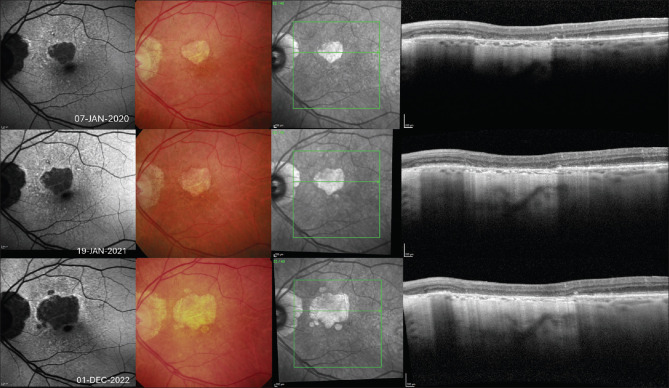

As we move toward an era in which there will be treatment options for geographic atrophy (GA) secondary to age-related macular degeneration, the need to accurately understand and interpret multimodal imaging (MMI) for the condition is paramount. This review discusses the evolution of MMI in GA and how it has led to a greater understanding of different phenotypes and risk factors for progression. These advancements have allowed novel imaging biomarkers to be used as end points in large interventional studies exploring new therapies for GA treatment. Due to differences in drug approval timing, ophthalmologists in some jurisdictions are already treating patients with complement inhibiting intravitreal therapies and using MMI to guide management. Cementing knowledge of how GA appears on MMI and evolves over time will be vital for best practice as these interventions become more widely available.